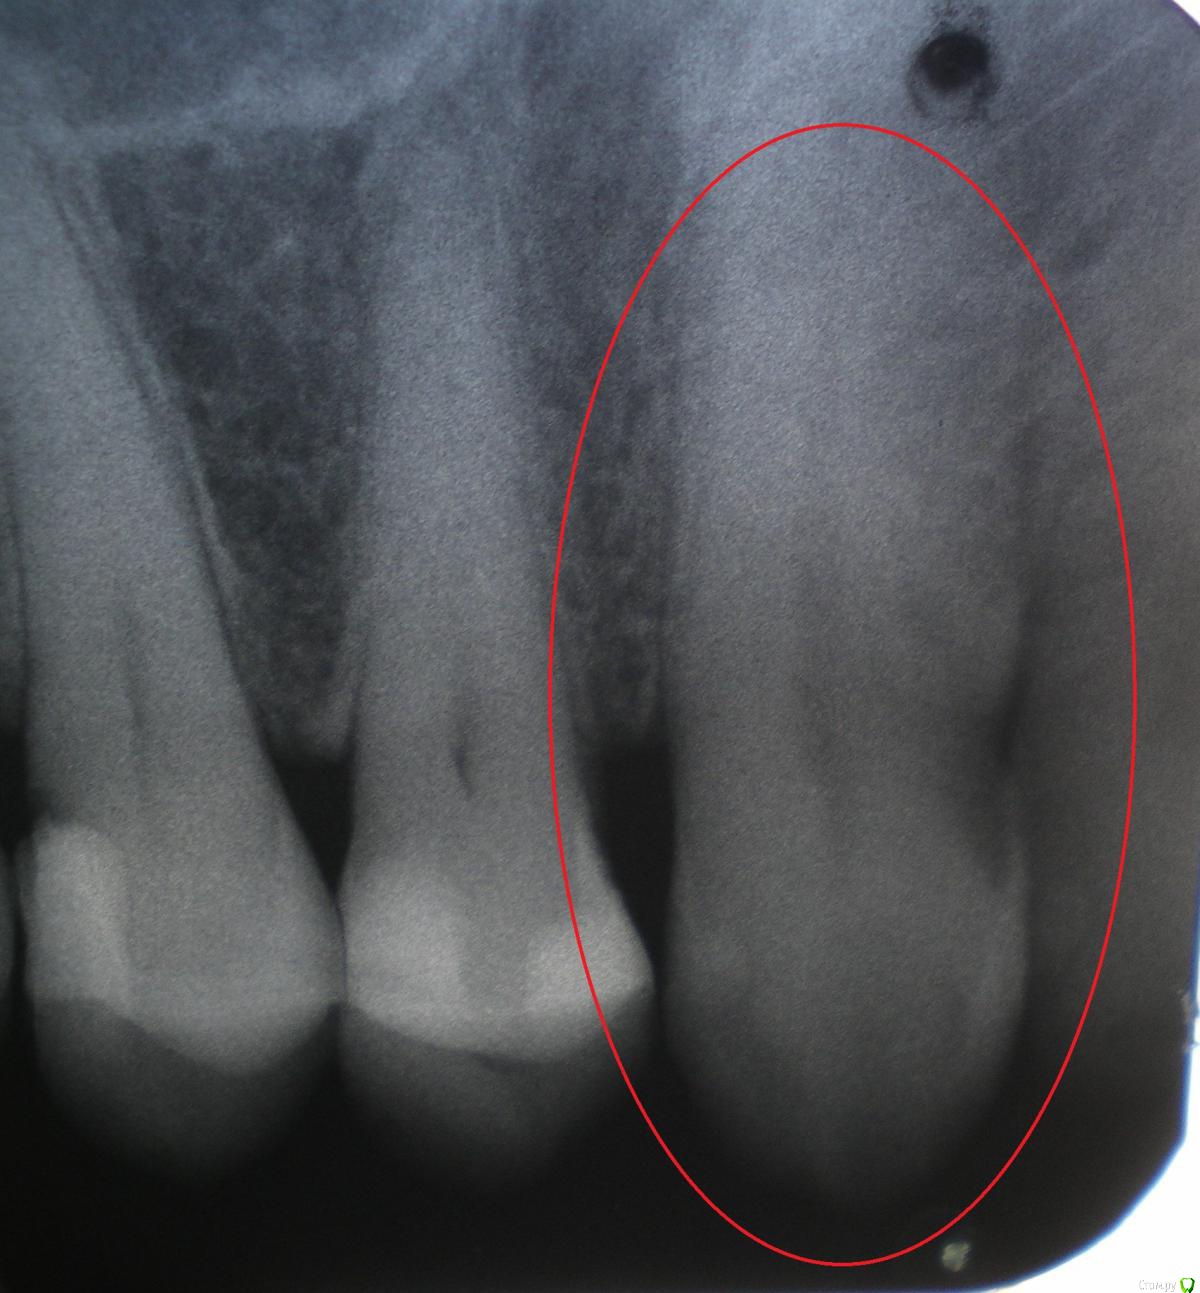

ganofer Опубликовано 21 мая, 2020 Поделиться Опубликовано 21 мая, 2020 Здравствуйте,подскажите по снимку, пожалуйста, не совсем понятно:на снимке (зуб выделен красной чертой) кариозная полость или зуб здоров?Спасибо. Ссылка на комментарий

red_butler Опубликовано 21 мая, 2020 Поделиться Опубликовано 21 мая, 2020 качество снимков не позволяет дать ответ Ссылка на комментарий